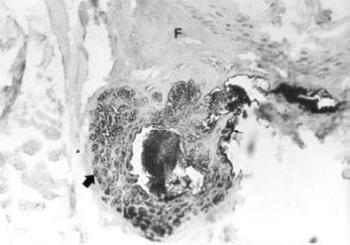

21. ábra. Epithelialis membrán antigén (EMA) kimutatása római kori múmia bőrében. Az EMA aktivitás csak a szőrtüszők sejtjeiben maradt meg (nyíl), a felhámban (F) nem. EMA-ABP immunhisztokémiai reakció, 200× nagyítás